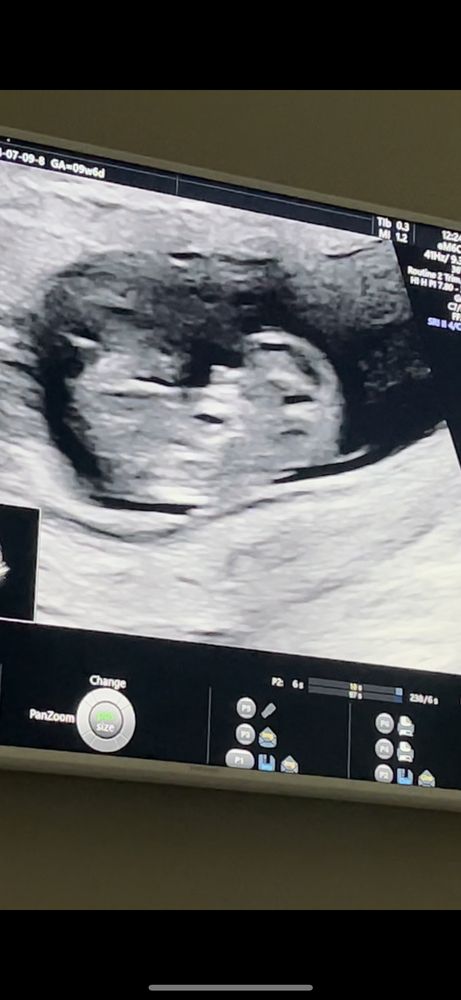

УЗИ, КТГ, доплерПокидайте фото своих малышей на 9-10 недельке. Как выглядели ваши малыши?

в интернете смотрю а там прям полноценные человечки, с носиками, с ручками.

Там уже не то что ручки и ножки, там уже танцульки и дрыгания во всю)) 9 и 6